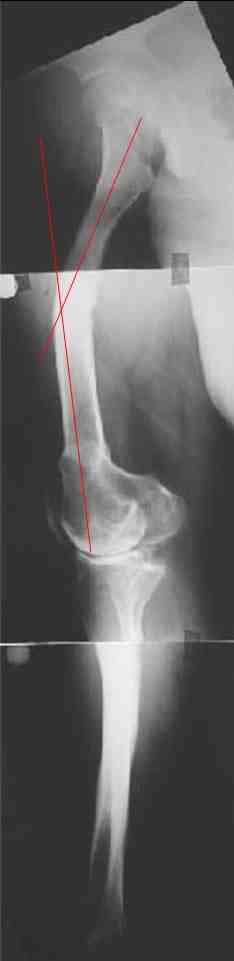

В данном случае перед эндопротезированием мы бы корригировали оси бедренной и большеберцовой костей (см. вложение). Дистальный эпидиафизарный угол бедра будет корригирован при эндопротезировании. Тип остеотомии и коррекции деформации (клиновидная резекция - одномоментная коррекция; формироване треугольных или трапециевидных регенератов во времени) - исходя из

относительной длины конечности.

На бедре дистальный отдел в сгибательной установке после, видимо, когда-то сделанной корригирующей остеотомии. Не надо ли на том же уровне все-таки "разогнуть" бедро до протезирования? Сам протез, наверно, можно поставить в большем или меньшем "сгибании", но весь дистальный эпиметафиз бедра и все нижележащее оказывается кзади от механической оси бедра. Насколько это допустимо, не ведет ли к расшатыванию протеза? Или можно как-то рассчитать такой наклон протеза, что он компенсирует это смещение?

Это один из самых сложных вариантов для эндопротезирования, т.к. мы имеем деформацию бедренной кости в трех проекция, думаю, что есть и

ротационная деформация, плюс к этому - деформация голени. Однозначно в таких случаях, в отличии от возможностей при эндопротезировании ТБС необходимо выполнить корригирующие остетомии на двух уровнях. Что касается сгибательно установки мыщелков бедра - думаю, что это не является проблемой, особенно если на операции будет испрользован заднестабилизированный протез. Относительно вальгуса - все не так однозначно - возможно, что деформация слегка преувеличена за счет проекционной установки из-за ротационной деформации. Поэтому планирование операции необходимо будет делать только после коррекции деформации.